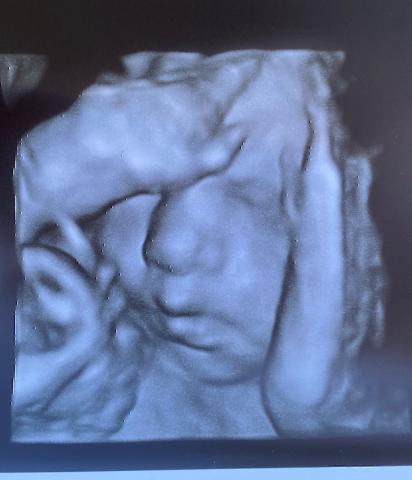

L’arrivée de notre petit Prince se rapprochant à grand pas, nous avons créé cette liste fictive afin que vous puissiez lui faire un cadeau si vous le souhaitez.

Merci d’avance et nous espérons très rapidement vous présenter notre petit Prince !